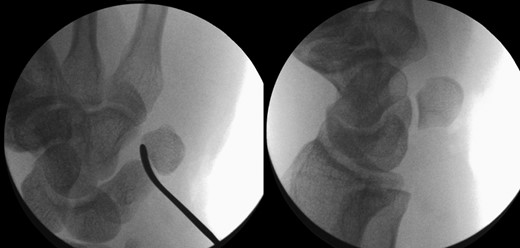

The X-rays of the patient was later reviewed by the duty radiologist and reported as a suspected dislocation of the pisiform bone, Fig. 1. Therefore the patient was recalled to the trauma clinic after three days. He was reassessed and a further three dimensional scan of the wrist was arranged. The CT scan demonstrated distal dislocation of the pisiform which appeared to lie in a ‘locked’ position beyond the distal triquetrum, Fig. 2.

CT showing pisiform displaced from its anatomical position confirming dislocation.

Image intensifier pictures showing reduction of dislocated pisiform bone.